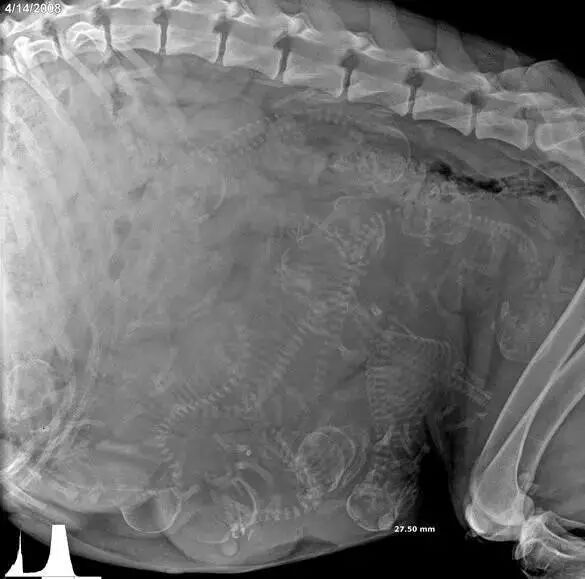

NO.9

<怀孕的豚鼠>

这些熊孩子,

几乎占据了所有腹腔。

当妈的辛苦啊!